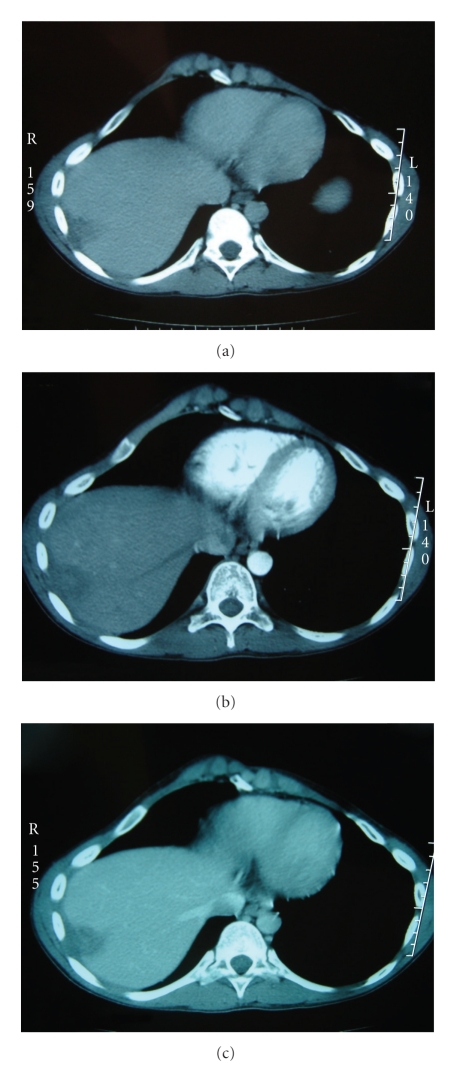

Abdominal tomography revealed a subcapsular lesion occupying segments VII and VIII and measuring 4 cm in diameter spontaneously hypodense and having slight peripheral enhancement at delayed stage (Figure 3).

Figure 3.

CT scan showing subcapsular lesion occupying segment VII and VIII and measuring 4 cm in diameter spontaneously low attenuated and having slight peripheral enhancement at delayed stage.